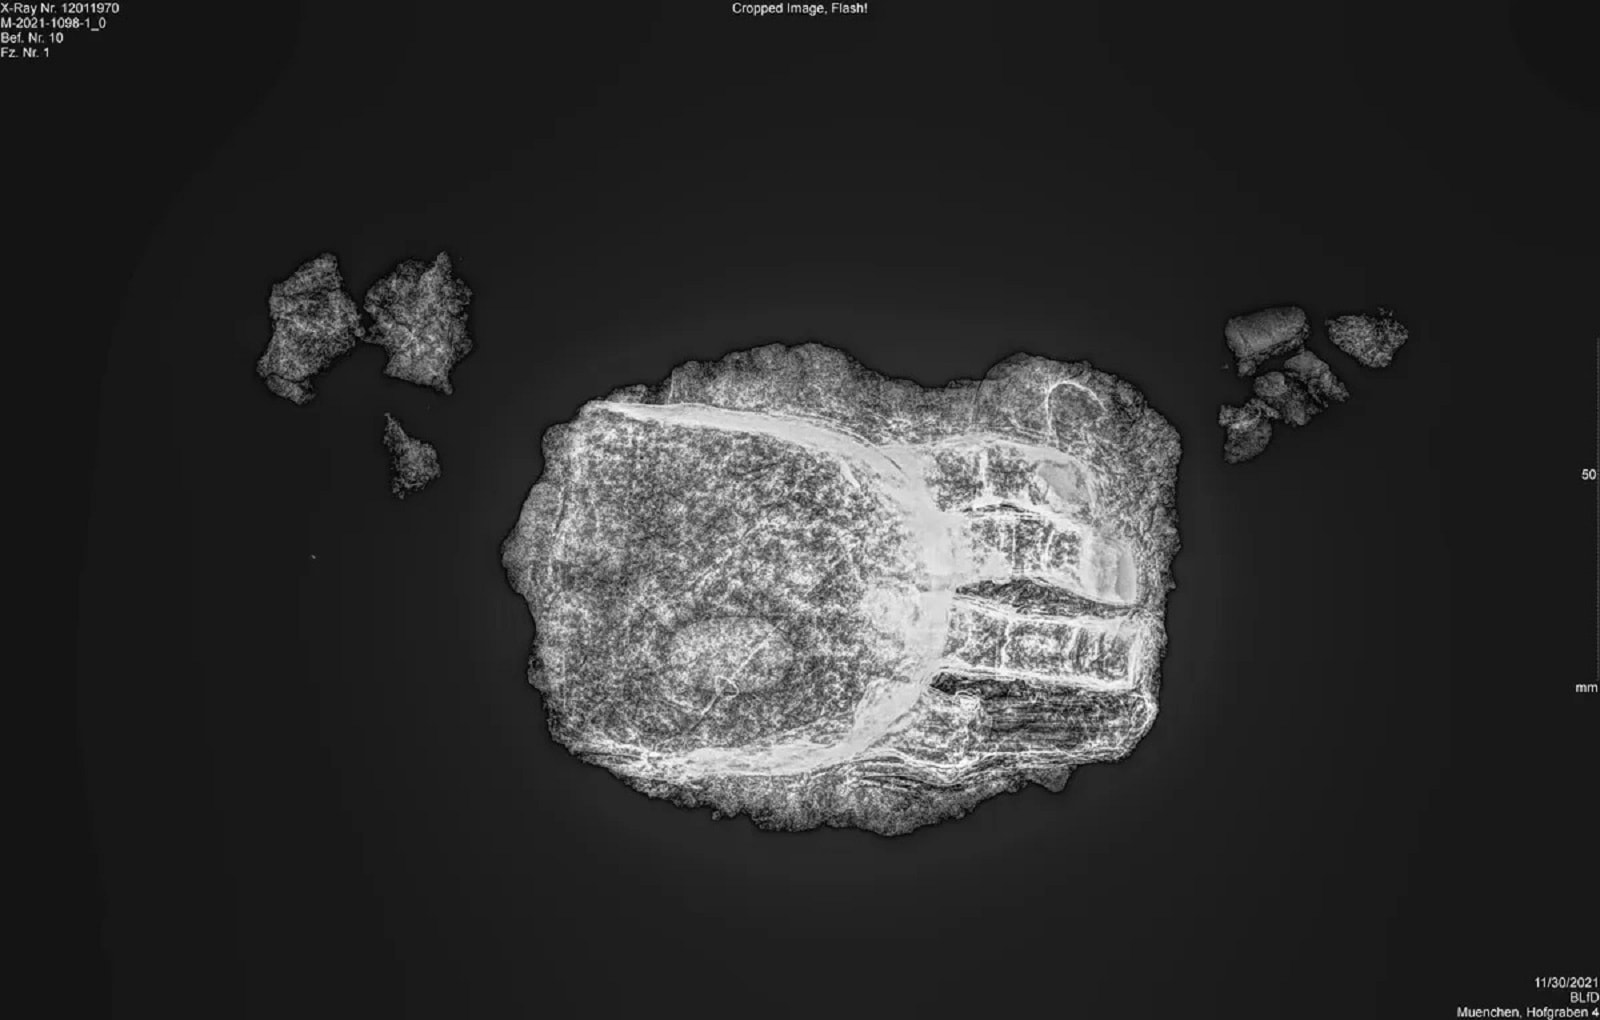

Działający tam archeolodzy dokonali przełomu w poszukiwaniach, gdy eksplorowali miejsca pochówku w bawarskim Freising. Ich oczom ukazał się szkielet połączony z protezą ręki, która powstała w okresie od 1450 do 1620 roku. Do jej wykonania użyto żelaza i metali nieżelaznych, a następnie pokryto skórą i zwieńczono replikami palców. Całość zachowała się w dobrym stanie i możemy mówić o jednym z najlepszych dowodów na rozwój średniowiecznej protetyki.

Zanim na miejscu zjawili się archeolodzy, obszar ich działań był objęty pracami budowlanymi w pobliżu jednego z lokalnych kościołów. Gdy wydobyto szkielet, uwagę ekspertów zwróciła obecność nietypowego elementu w obrębie lewej dłoni zmarłego. Jak się okazało dzięki przeprowadzonym ekspertyzom, palce tej osoby zostały amputowane, a do dyspozycji pozostawiono jej wyłącznie kciuk.

W miejsce pozostałych palców wprowadzono natomiast protezę. Puste obszary wyścielono miękkim materiałem, którego pozostałości zachowały się do dziś. Innymi słowy, pozbawiony części kończyny człowiek zyskał możliwość wykonywania prostych czynności wymagających użycia palców. Zdaniem archeologów ta niezwykła proteza została zaprojektowana tak, aby dało się ją połączyć z fragmentem dłoni. Wydaje się, że pomagała ona w codziennym funkcjonowaniu i nie miała wyłącznie odpowiadać za aspekty wizualne.

Co wiemy o samym zmarłym? W momencie śmierci miał od 30 do 50 lat. Mężczyzna ten zamieszkiwał tereny współczesnych Niemiec gdzieś pomiędzy 1450 a 1620 rokiem, co wywnioskowano w oparciu o datowanie szczątków metodą radiowęglową. Warto podkreślić, że to nie pierwsze takie znalezisko na Starym Kontynencie. Jak na razie archeolodzy działający w Europie wiedzą o około 50 podobnych protezach. Niektóre były nieruchome, podczas gdy inne pozwalały na wykonywanie pewnych manewrów.